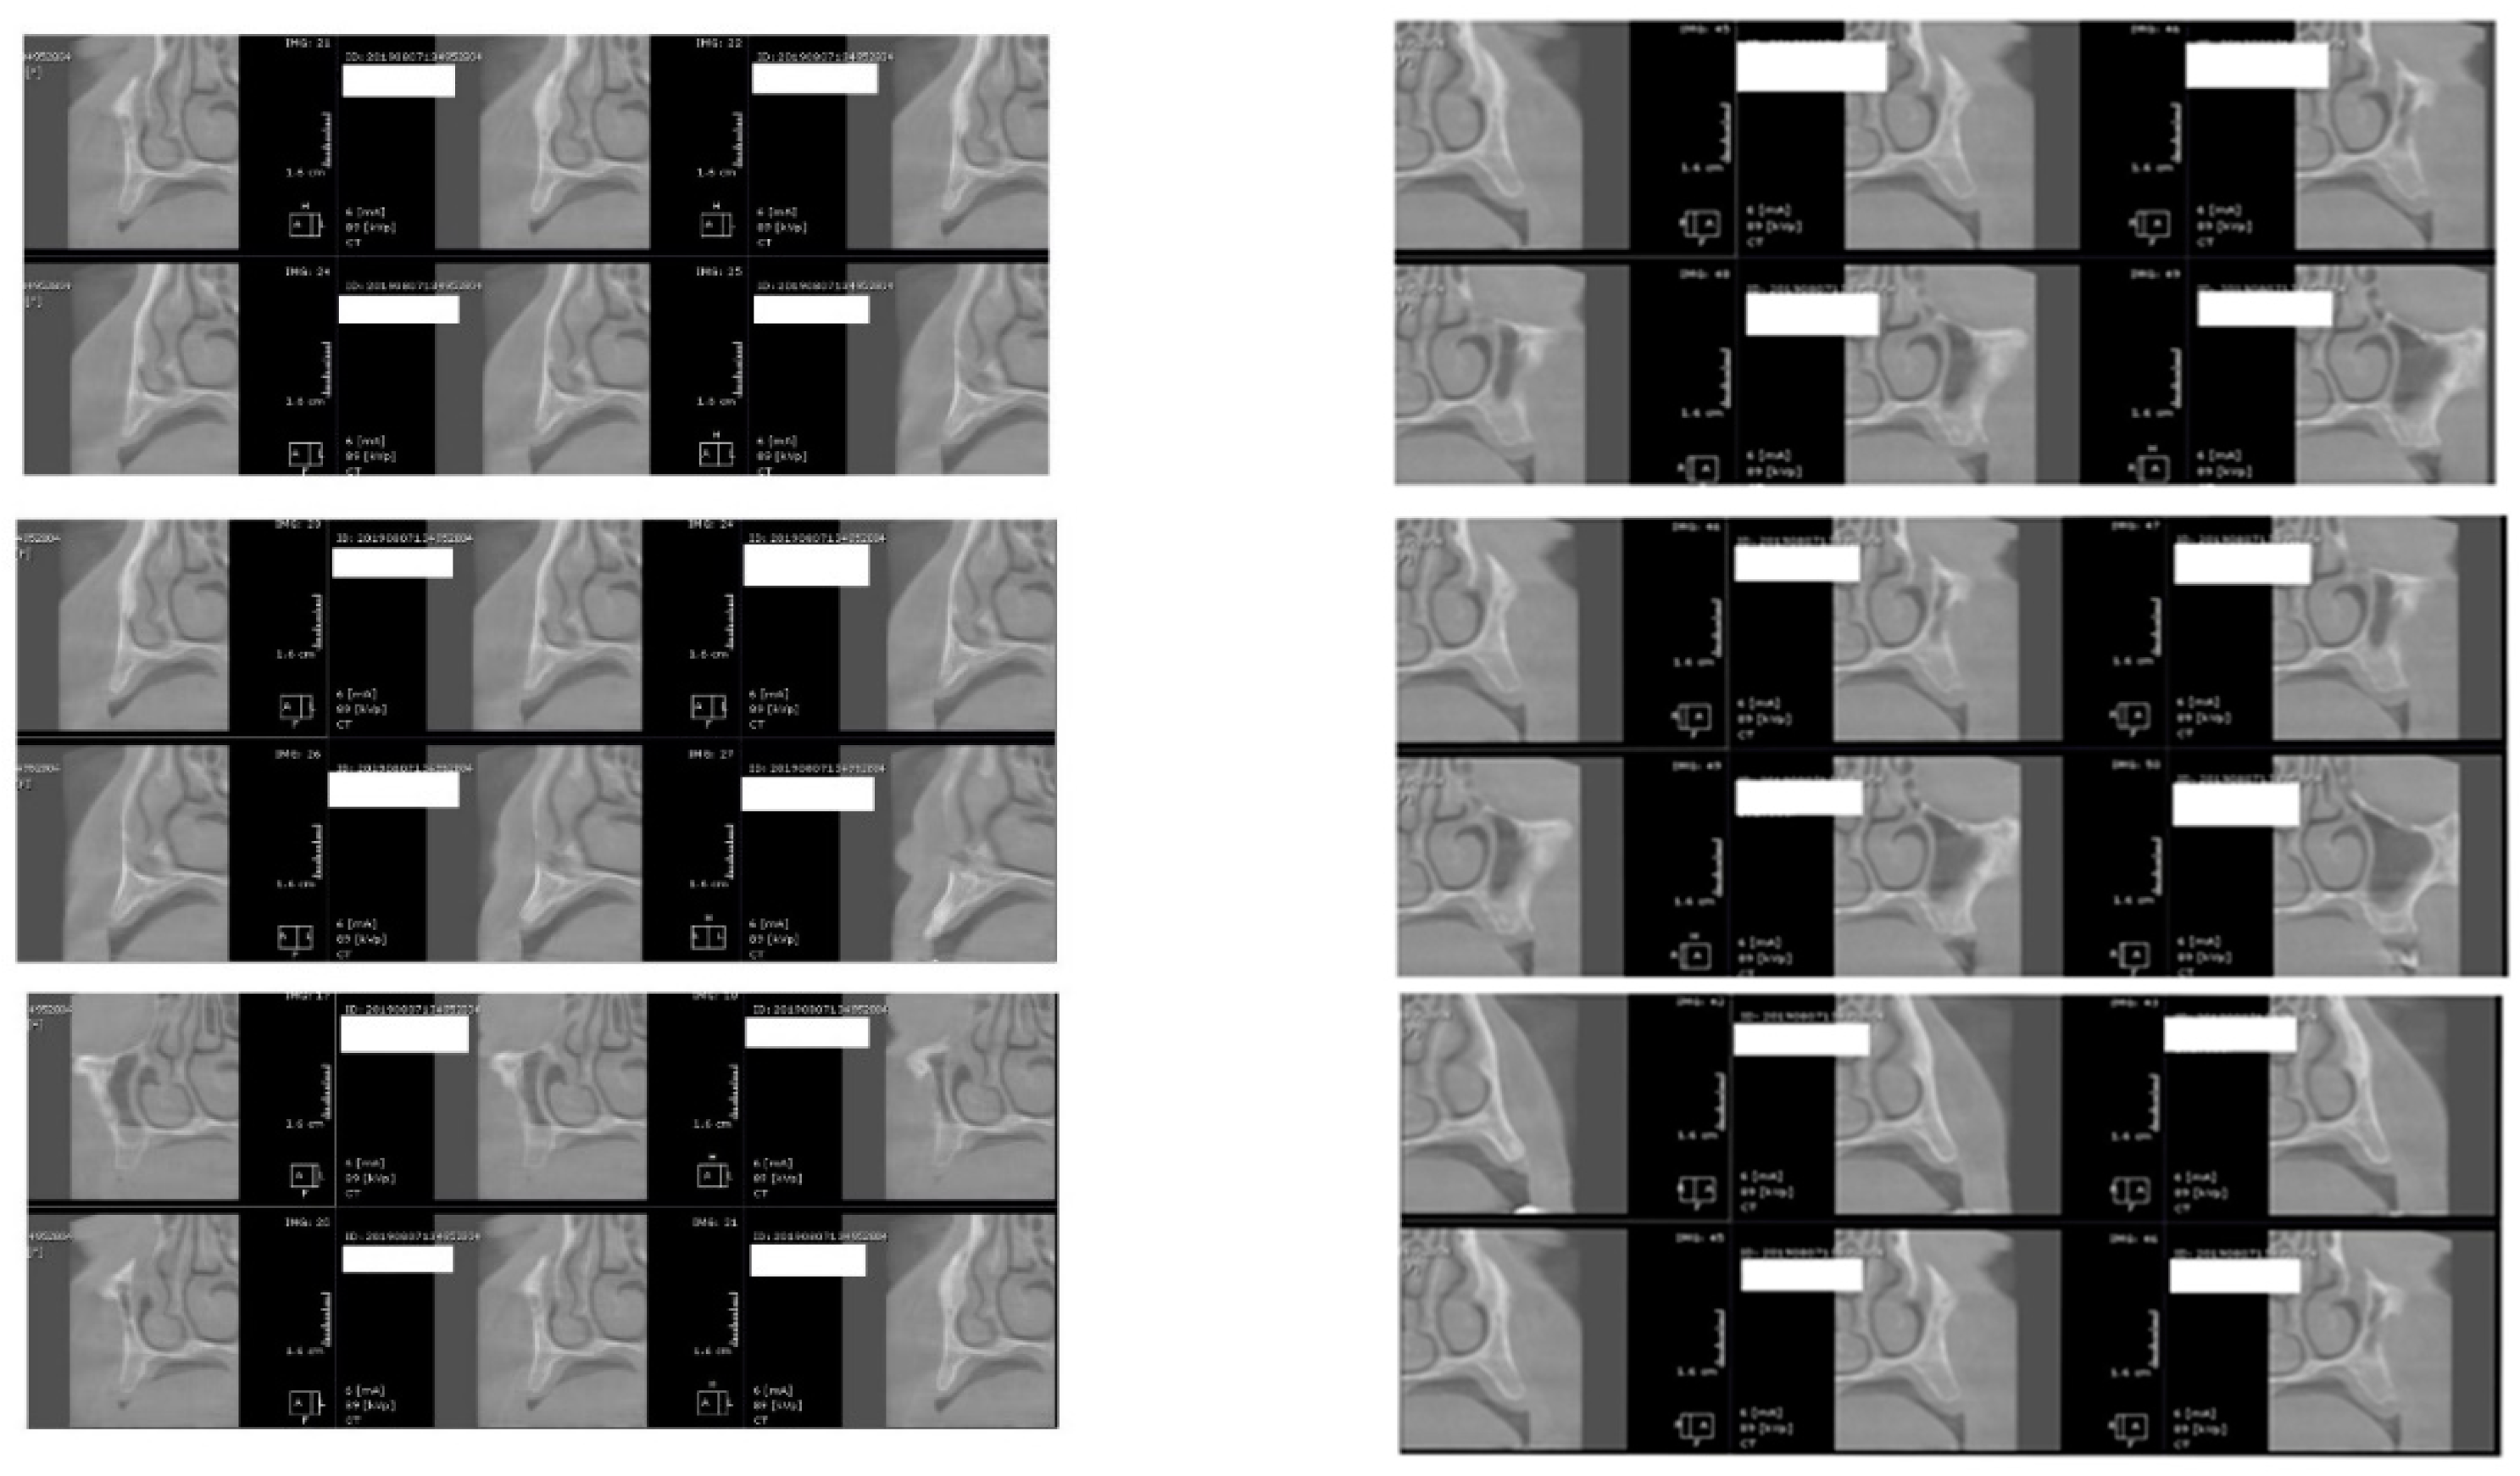

For image acquisition, we used a ProMax 3D CBCT unit (Planmeca, Helsinki, Finland), with the previously mentioned settings. Images were acquired and saved in JPEG format. To locate implant target sites, bone density, and to record the mean CT number of the trabecular bone from these sites, we used the OnDemand 3Ddata App™ software (Cybermed Inc., Seoul, South Korea). In each site, our region of interest was a square volume of bone located within the alveolar ridge (Figure 3, Figure 4 and Figure 5). All data recorded were input into the Microsoft Office Excel™, 2017 version, analysis software (Microsoft, Redmond, WA, USA).

Figure 3.

CBCT images used in the study, showing sagittal sections of bone.

Figure 4.

CBCT images used in the study showing the density of bone.